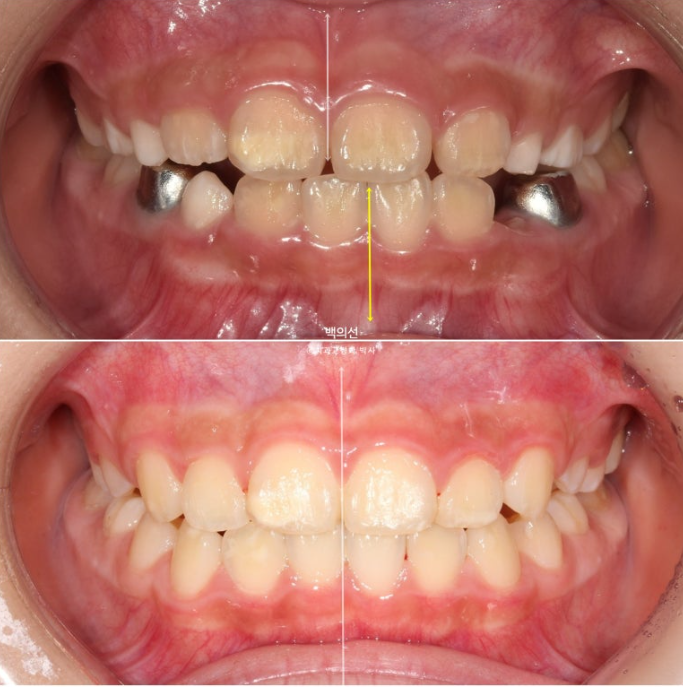

앞니 중심선이 맞지 않고

엑스레이에서 아래턱의 골격적 비대칭으로 진단이 되었습니다.

23.12

인비절라인퍼스트 치료를 권유드렸고 아래턱의 위치를 중앙으로 재위치시키는 Mandible Advance(MA) 기능을 통해 비대칭 개선을 목표로 치료계획을 세웠습니다.